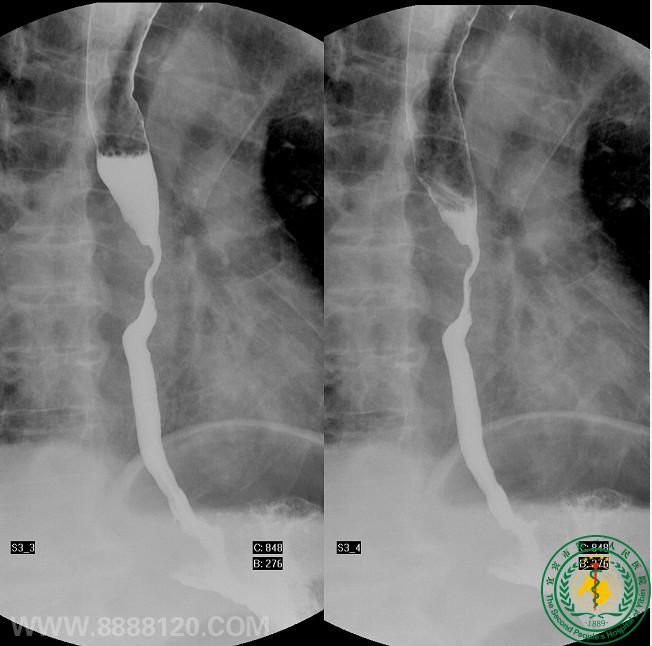

影像科介入室开展首台DSA下食道支架置入术

影像科介入室开展首台DSA下食道支架置入术1702